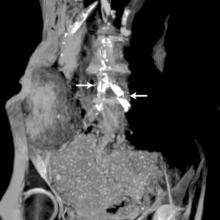

New research published in June issue of Global Heart (the journal of the World Heart Federation) show that there are no significant differences in the incidence or severity of atherosclerotic disease (narrowing of the arteries with fatty deposits) between ancient and modern people, showing that atherosclerosis is not just a disease of modern times. The journal included three articles [1,2,3] on the finding of the HORUS Study, which used CT scans from ancient mummies to compare arterial calcification caused by HORUS atherosclerosis.